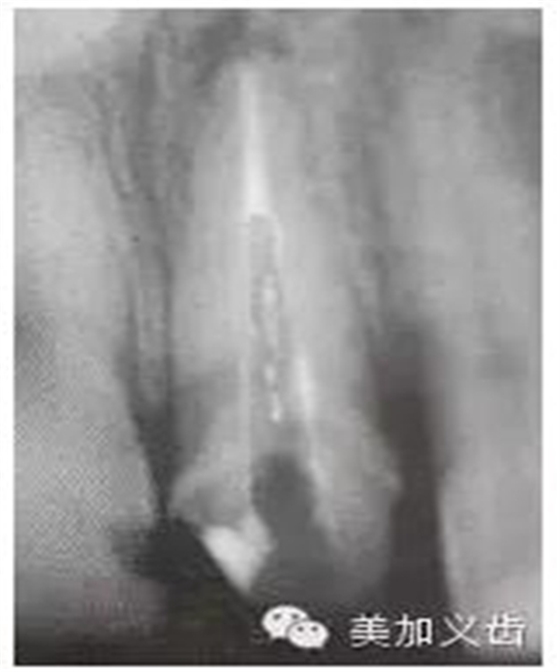

預(yù)備后根管壁上會不同程度的牙膠和封閉劑等殘留物,所以樁道預(yù)備前后建議X線片輔助檢查預(yù)備深度等情況,而殘留物也會很清晰地顯現(xiàn)。